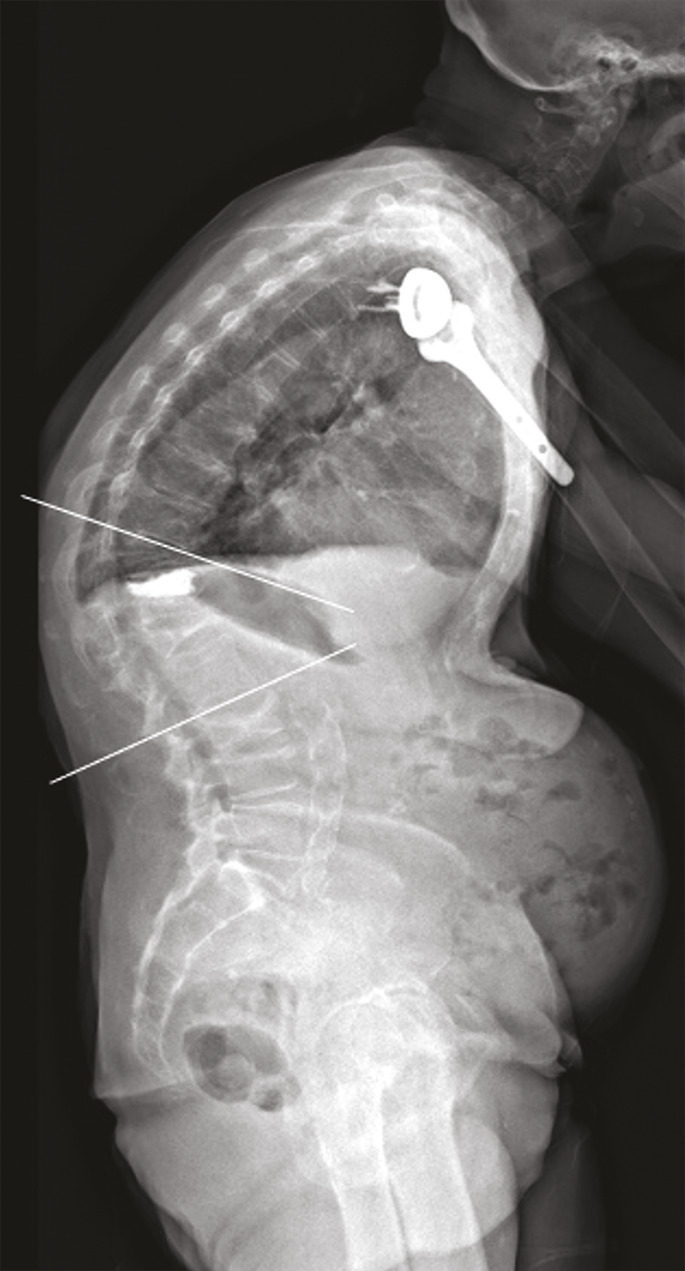

Le plus souvent, les fractures ostéoporotiques consolident et les douleurs peuvent être gérées par le ­traitement médical avant de disparaître spontanément en quelques semaines. Dans certains cas cependant, la pérennisation des douleurs requiert des morphiniques et contraint le patient à un alitement prolongé, avec les risques inhérents chez une personne âgée. La fracture peut aussi se majorer progressivement, ce qui peut entraîner une perte importante de hauteur du corps vertébral et majorer la cyphose. Parfois encore, chez le sujet âgé, la fracture ne consolide pas et une véritable pseudarthrose, avec image de « vide » (gaz) intrasomatique se constitue, source de douleurs mécaniques et d’évolution prolongée. On peut alors observer, sur les radiographies et en scanner, une image cavitaire ­linéaire intracorporéale qui peut contenir du gaz (fig. 5), ainsi qu’un signal liquidien en IRM.

La présence de fractures incidentes augmente le risque de nouvelles ­fractures. Outre les douleurs, la ­multiplication des fractures vertébrales peut avoir des conséquences très délétères sur la statique rachidienne : perte de la lordose lombaire et augmentation de la cyphose thoracique. En particulier, les fractures de la charnière thoraco-lombaire, siège de prédilection des fractures ostéoporotiques, à la jonction d’un segment rachidien relativement fixe et d’un segment mobile, entraînent souvent une cyphose angulaire importante et préjudiciable sur le plan fonctionnel. Une seule fracture cunéiforme de la charnière thoraco-lombaire ou du rachis thoracique inférieur peut même générer 15 à 20° de cyphose, ce qui est loin d’être anodin.21 La cyphose vertébrale est un marqueur du vieillissement physiologique et un facteur de morbidité, du fait du déséquilibre sagittal du rachis, de la diminution des capacités fonctionnelles et respiratoire, de la majoration du risque de chute et donc de nouvelles fractures (fig. 6) ; elle accroît le risque de ­mortalité. La cyphose crée aussi un cercle vicieux mécanique : chaque fracture vertébrale l’accroît et majore le déséquilibre antérieur du rachis, la charge sur les autres vertèbres et donc le risque de nouvelle fracture. L’influence de la cyphose thoracique, sur le risque de fracture vertébrale incidente et sur la qualité de vie a été évaluée prospectivement sur 3 ans, dans une population de 1 624 femmes ménopausées ostéoporotiques non traitées.22 Une cyphose plus importante (quelle qu’en soit la cause) est un facteur de risque important et indépendant de nouvelle fracture vertébrale et d’altération de la qualité de vie.22 On sait aussi, depuis de récentes études épidémiologiques, que les fractures vertébrales ostéoporotiques sont associées à une surmortalité.23

L’objectif d’une cimentoplastie ­percutanée (vertébroplastie et kyphoplastie à ballonnets) est double : antalgie et lutte contre la cyphose et le déséquilibre rachidiens. La vertébroplastie percutanée (fig. 5) consiste à injecter par voie transpédiculaire, dans le corps vertébral fracturé, un ciment acrylique (polyméthylmétacrylate) qui est de même nature que celui que l’on utilise pour sceller les prothèses ­articulaires, et dont la tolérance ­biologique est bien établie. Dans la cyphoplastie (ou kyphoplastie) à ­ballonnets (fig. 7), l’injection est précédée d’une tentative de réexpansion du corps vertébral fracturé, grâce à des ballonnets gonflables afin de regagner une partie de la hauteur perdue et de réduire la cyphose.

L’objectif premier de ces deux techniques est antalgique. Consolider le corps vertébral et soulager les patients invalidés par des douleurs, intenses et persistantes, permet leur remise en charge et la prévention des complications du décubitus. Dans les cas favorables, la consolidation de la fracture et la diminution des douleurs permettent au patient de retrouver une mobilité. La consolidation de la fracture joue un rôle particulièrement important dans les fractures pseudarthrosées avec « vide intrasomatique » (fig. 5). La ­vertébroplastie et la kyphoplastie permettent aussi d’éviter que la fracture progresse (fracture en deux temps) et que l’angle de cyphose ­augmente, ce qui est fréquent. Elles réduiraient aussi la surmortalité associée aux fractures vertébrales.23

La vertébroplastie et la kyphoplastie n’évitent pas l’évolution de l’ostéoporose fracturaire, avec de nouvelles fractures, notamment vertébrales, et une aggravation progressive de la cyphose (fig. 6). Aussi, s’il faut prendre en charge les fractures ostéoporotiques, il ne faut pas oublier de traiter la maladie de fond : l’ostéoporose. Il existe maintenant des traitements médicaux de l’ostéoporose fracturaire qui, dans l’ensemble, diminuent au moins par deux le risque de nouvelles fractures. Devant une fracture ostéoporotique, vertébrale ou extravertébrale, il faut systématiquement les instaurer, en sus de la correction d’une carence en vitamine D, très souvent associée.